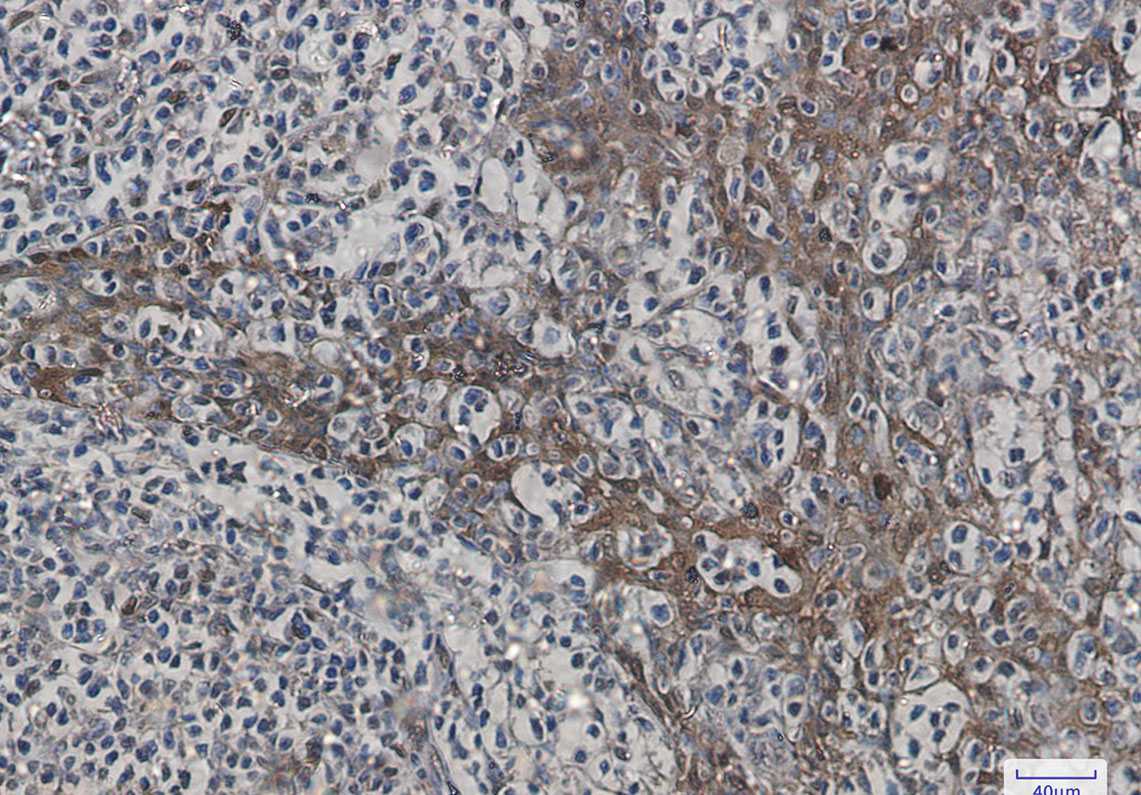

Immunohistochemistry analysis of paraffin-embedded Human tonsil using Hsp70 antibody.High-pressure and temperature Sodium Citrate pH 6.0 was used for antigen retrieval.